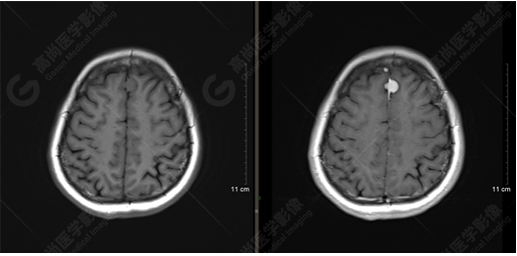

以上是常規(guī)顱腦MRI對病灶作出的診斷,可以看出,患者橋腦及大腦鐮各有一病灶,那么兩個病灶是否對顱腦神經(jīng)纖維束走行都有影像呢,下面是橋腦病變附近的神經(jīng)纖維束成像——皮質(zhì)脊髓束:

DTI成像示皮質(zhì)脊髓束橋腦段受壓向外側(cè)移位。圖像能清楚的顯示神經(jīng)纖維束與病灶的關(guān)系,是一種推壓移位的表現(xiàn)。